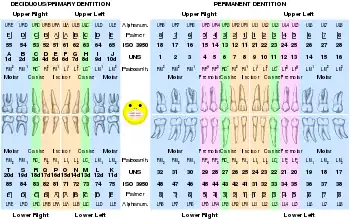

Dental professionals, in writing or speech, use several different dental notation systems for associating information with a specific tooth. The three most common systems are the FDI World Dental Federation notation (ISO 3950), the Universal Numbering System, and the Palmer notation. The FDI notation is used worldwide, and the Universal is used widely in the United States. The FDI notation can be easily adapted to computerized charting.

FDI World Dental Federation (ISO) notation

The FDI World Dental Federation notation ("FDI notation" or "ISO 3950"[1]) is widely used by dental professionals internationally to identify and describe a specific tooth.

The FDI notation uses a two-digit numbering system in which the first digit represents a tooth's quadrant and the second digit represents the number of the tooth from the midline of the face. For permanent teeth, the patient's upper right teeth begin with the number "1", the upper left teeth begin with the number "2", the lower left with "3", and the lower right with "4". For primary teeth, the sequence of numbers similarly is 5, 6, 7, and 8 for the teeth in the upper right, upper left, lower left, and lower right respectively. When speaking about a certain tooth such as the permanent maxillary central incisor, the notation is pronounced “one, one”.

Permanent dentition

patient's upper right – 1 upper left – 2

18 17 16 15 14 13 12 11 | 21 22 23 24 25 26 27 28

R --------------------------------------------------- L

48 47 46 45 44 43 42 41 | 31 32 33 34 35 36 37 38

lower right – 4 lower left – 3

Primary dentition

upper right – 5 upper left – 6

55 54 53 52 51 | 61 62 63 64 65

R --------------------------------- L

85 84 83 82 81 | 71 72 73 74 75

lower right – 8 lower left – 7

FDI notation: quadrants of the teeth

FDI notation: quadrants of the teeth ISO notation upper jaw

ISO notation upper jaw ISO notation lower jaw

ISO notation lower jaw ISO notation primary teeth

ISO notation primary teeth